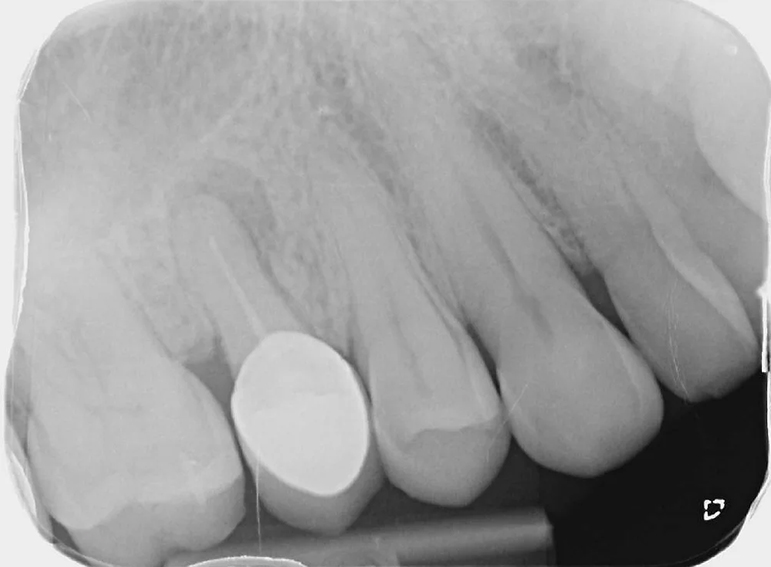

Removal of infected premolar and replacement with a temporary adhesive bridge and implant.